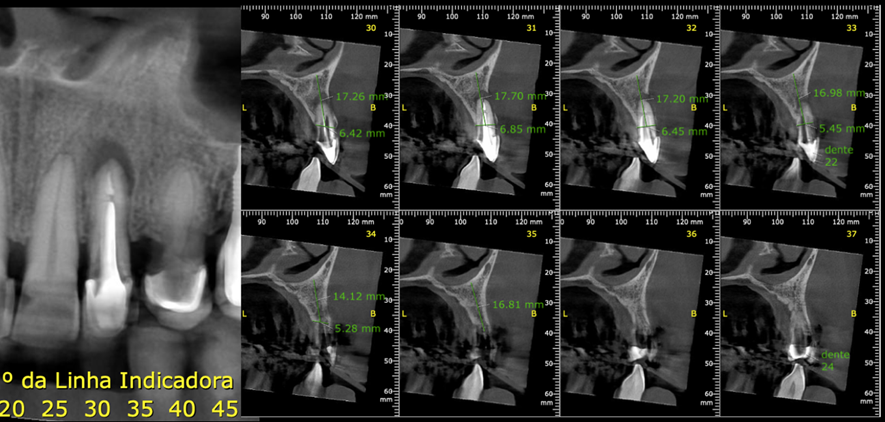

A seguir, as figuras 1 a 5 ilustram o caso: